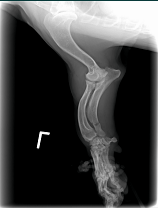

Hey Bob,Sorry, Ive been in and out of town.  I've attached some radiographs of a 12 year-old dog with an ulnar fracture we've been using it on.  It looks like we have significant callous formation in 16 days!  I have another dog that I did a patellar luxation surgery that we are using it on as well.  I'll try to get you some films of it.  So far I haven't had any major issues.  It would be nice if the device itself could be smaller for some of these smaller dogs.  The fracture dog has a bandage/splint on, so it is pretty easy to encorporate the coils into the bandage.  The other dog has no bandage, so I've been using elasitcon to hold it over the affected area.  After a 4-5 days it causes some irritation and we have the device off a couple of days before replacing it.  I'm not sure there is any other way to hold it there(over the knee) without putting a bandage over the leg which would limit our range of motion and cause muscle atrophy.Thanks,

Ian Voeizel, DVM